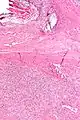

| Micrograph of a solitary fibrous tumor. H&E stain. | |